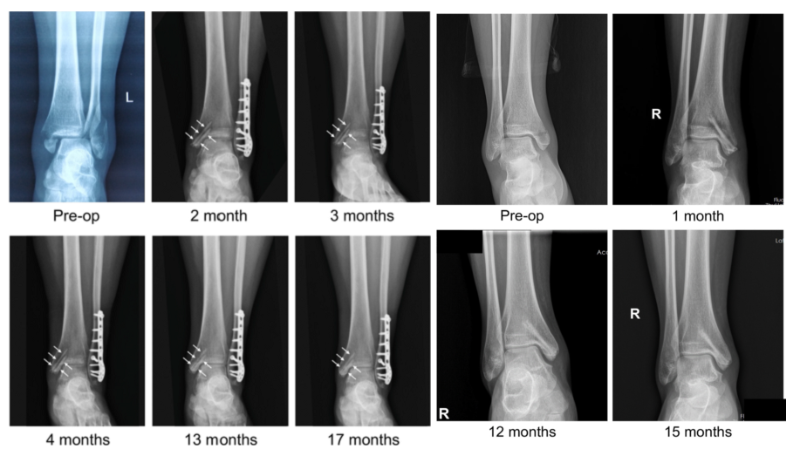

近日,國際骨科臨床轉(zhuǎn)化期刊《Journal of Orthopaedic Translation》在線發(fā)表了由上海交大戴尅戎院士、郝永強(qiáng)教授團(tuán)隊(duì)和丁文江院士、袁廣銀教授團(tuán)隊(duì)合作發(fā)表的可降解鎂合金骨釘1-2年的臨床試驗(yàn)觀察結(jié)果,所有患者術(shù)后內(nèi)踝骨折愈合,功能恢復(fù)。研究證實(shí)了可降解鎂合金螺釘治療內(nèi)踝骨折的臨床療效及其生物安全性,為全降解鎂合金植入物等高端醫(yī)療器械進(jìn)一步的臨床推廣應(yīng)用奠定了堅(jiān)實(shí)基礎(chǔ),相關(guān)成果以“Effectiveness and safety of biodegradable Mg-Nd-Zn-Zr alloy screws for the treatment of medial malleolar fractures”為題在線發(fā)表于Journal of Orthopaedic Translation,27 (2021) 96–100。這是國內(nèi)首個可降解醫(yī)用鎂合金臨床試驗(yàn)的公開報(bào)道,也是國際首款含有功能涂層的可降解鎂合金骨釘?shù)呐R床試驗(yàn)結(jié)果的公開報(bào)道,具有里程碑意義。

醫(yī)用鎂合金骨內(nèi)植物臨床試驗(yàn)研究突破性進(jìn)展(圖1)